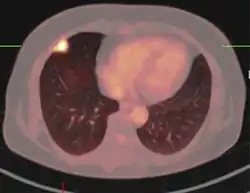

PET-CT of a tuberculoma